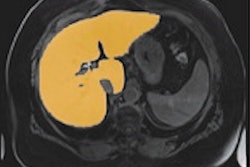

For individualized tumor therapy, Diedrich wrote that imaging is decisive when it comes to pre-treatment choices, such as with chemotherapy, radiation, or both, as well as predicting success and follow-up.

"With methods such as perfusion CT and MRI, measurement of the apparent diffusion coefficent value or PET-CT, it is possible to make a statement very early, after a week or, in the best case, after one day, whether the tumor responds to therapy," he added.